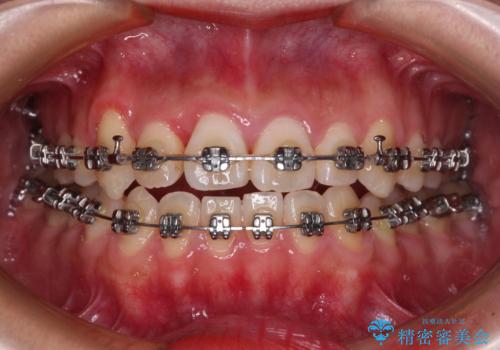

- 矯正装置

- メタルブラケット

上顎歯列が狭窄していたため、急速拡大装置により上顎骨を側方に拡大し、その後ワイヤー装置にて矯正治療を行うこととしました。

上顎骨を拡大することで、八重歯やデコボコを歯列に収めることができ、下顎の歯が外に位置していた奥歯の咬み合わせも改善することができました。

スペースも短期間に獲得できるため、1年程度で治療を終えることができました。